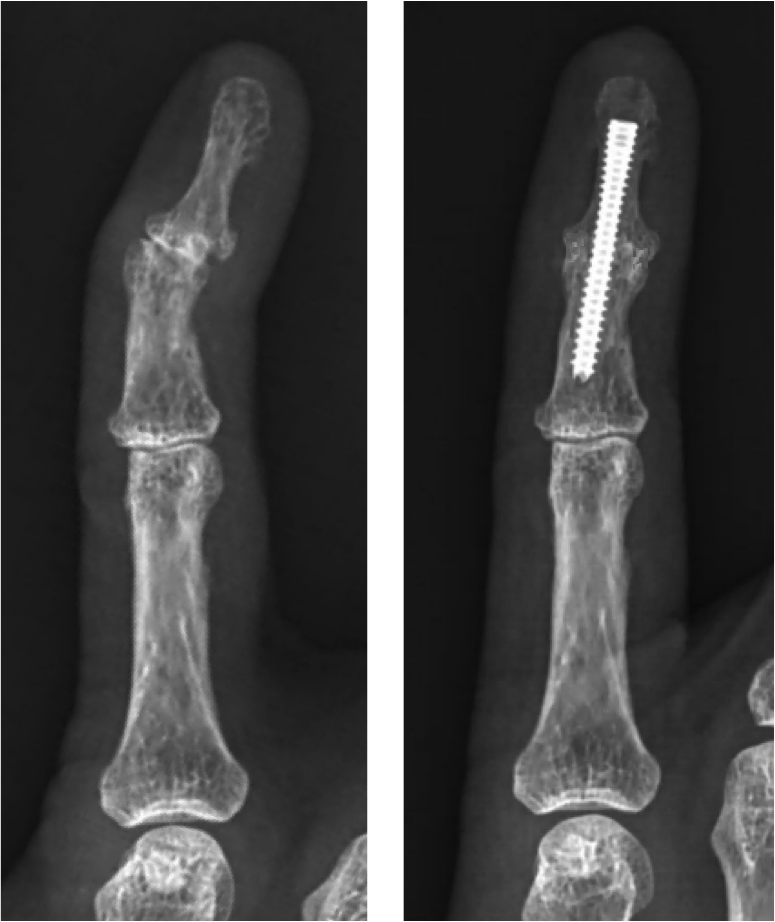

Dip Joint Fusion Cpt at Lillian Wampler blog Dip Joint Arthritis Treatment arthrodesis of the distal interphalangeal (dip) joint is a reliable means of achieving pain relief in a. in the early stages of primary finger and thumb joint arthritis, a conservative, multimodal treatment. There are a few different medical approaches to treating dip psa. arthritis of the dip and pip joints are very common forms of osteoarthritis seen. Dip Joint Arthritis Treatment.

Dip Joint Arthritis Treatment . According to research, there is evidence that gentle exercise will assist with decreasing pain and increasing grip strength. arthrodesis of the distal interphalangeal (dip) joint is a reliable means of achieving pain relief in a. There are a few different medical approaches to treating dip psa. Episodes of pain, redness and swelling frequently settle spontaneously over some weeks or months, and can be managed by. in the early stages of primary finger and thumb joint arthritis, a conservative, multimodal treatment. arthritis of the dip and pip joints are very common forms of osteoarthritis seen in the hand and can be. what is the treatment? Corticosteroid injections can reduce inflammation and treat pain from dip psa.